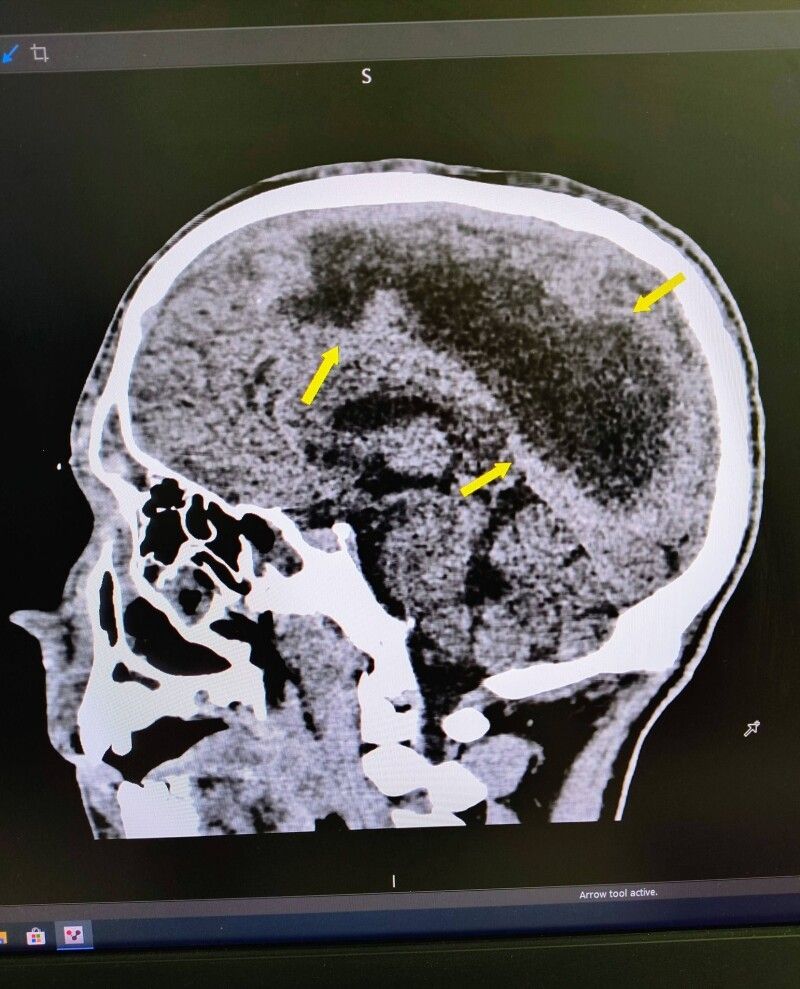

«Пацієнт поступив до нас у стані глибокої коми. За даними КТ в дитини була емпієма, тобто масивне скупчення гною над правою півкулею головного мозку. Ми провели оперативне втручання, дренувавши вміст емпієми, тобто забрали гній з мозку», — розповідає нейрохірург Лікарні Святого Миколая Юрій Кузьмінський.

Звідки взявся гній у головному мозку дитини з'ясували вже наші ЛОР-спеціалісти. До такого важкого стану призвів синусит, тобто запалення приносових пазух, яке виникло як ускладнення застуди. Через порушення відтоку слиз перетворився на гній – виникли гайморит та фронтит. А далі гній, якому не було куди відходити, пішов у мозок та очні ямки.